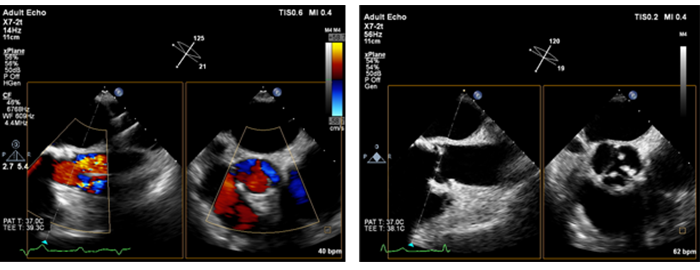

您只需要触摸按钮,就可以使用 xMATRIX 单探头的所有模式:二维、三维 / 四维、实时三维超声心动、实时双平面成像 (xPlane)、实时三维放大、实时三维全容积、iRotate、实时多平面重建、多平面重建、M 模式、多普勒、彩色多普勒和 CPA。无需中断采集以切换探头。您可以在您的 PACS 系统中查看超声 xMATRIX 容积数据,和查看 CT 和磁共振图像一样。一旦获取数据,只需一键,系统就会将获取到的 X、Y、Z 轴或 iSlice 多平面重建影像传输至 PACS 系统。随时查看、分层和询问,以适应您的日程安排。

实时双平面成像 可以同时创建两个全分辨率平面,让您可以在相同的时间内获取比传统二维成像多一倍的临床信息。

在心脏检查过程中,实时任意多平面成像使您能够在一个心动周期内同时采集两个平面的图像,快速准确地获取关键信息。